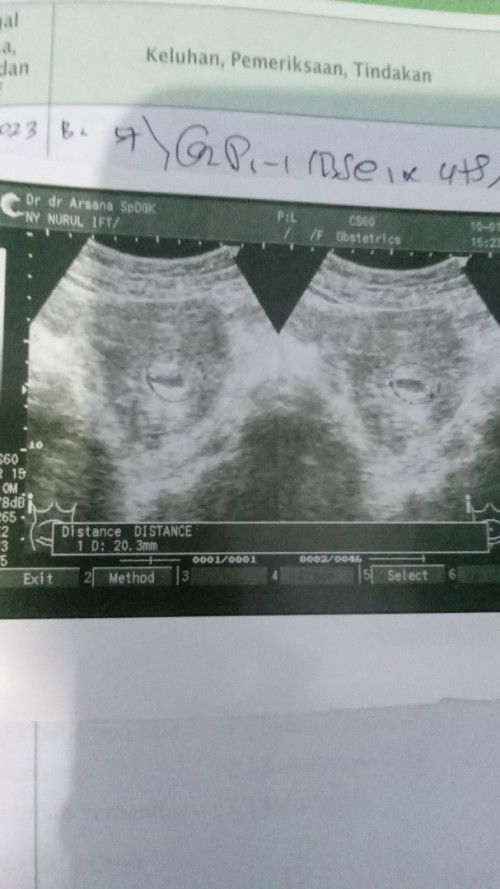

Pendarahan sebentar hamil 6W

Usia kandungan 6W, tiba² kmrin siang ada darah coklat netes bun tapi cuman sbntar. Langsung USG kata dokter berpotensi keguguran kmdian dikasih obat penguat & istirahat total bun. Semoga tdk keluar darah lagi ya bun 🤲 Adakah harapan saya mempertahankan janin ini bun? Hasil USG 6W5d masih blm terlihat janin, wajar kah??